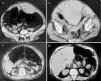

Se trata de una mujer de 73 años que ingresó en un hospital comarcal a causa de dolor abdominal súbito coincidiendo con ataques repetidos de tos. La paciente estaba siendo tratada con acenocumarol y digital por fibrilación auricular y por ser portadora de una prótesis mitral metálica. A la exploración, la paciente estaba pálida y se palpaba una masa redondeada en la zona infraumbilical izquierda. Los principales datos analíticos revelaron una hemoglobina de 9,8 g/dl, un hematocrito del 29% y un ratio internacional normalizado (INR) de 9,4. Una ecografía abdominal mostró una masa líquida paraumbilical izquierda sugestiva de HVR. El tratamiento anticoagulante fue suspendido y se administraron concentrados de hematíes, plasma fresco congelado y vitamina K. A las 24 horas del ingreso y ante el aumento del tamaño de la masa abdominal se realizó una TC de abdomen sin contraste (fig. 1) que demostró un HVR izquierdo extendiéndose en el interior de la pelvis, una relación del diámetro abdominal anteroposterior y transverso de 0,82 y AVP hepático. Posteriormente, la paciente fue trasladada a la Unidad de Cuidados Intensivos (UCI).

Figura 1. Tomografía computarizada abdominal sin contraste que muestra, sobre la línea arcuata, un hematoma de la vaina del recto izquierdo (A) y bajo la línea arcuata su extensión en la pelvis menor con compresión de la vejiga urinaria y el útero (B). Donde la vena renal izquierda cruza la aorta existe una relación del diámetro anterosuperior-transversal de 0,82 (C), y a nivel hepático se observan zonas tubulares radiotransparentes en la periferia del hígado compatibles con aire en el interior de las venas intrahepáticas (D).